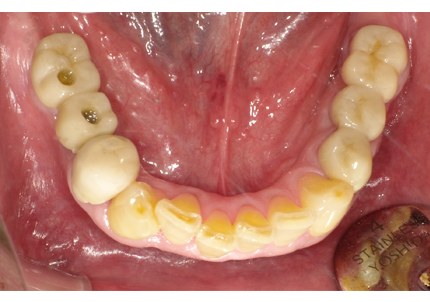

1.初診時口腔内写真(2014年6月)